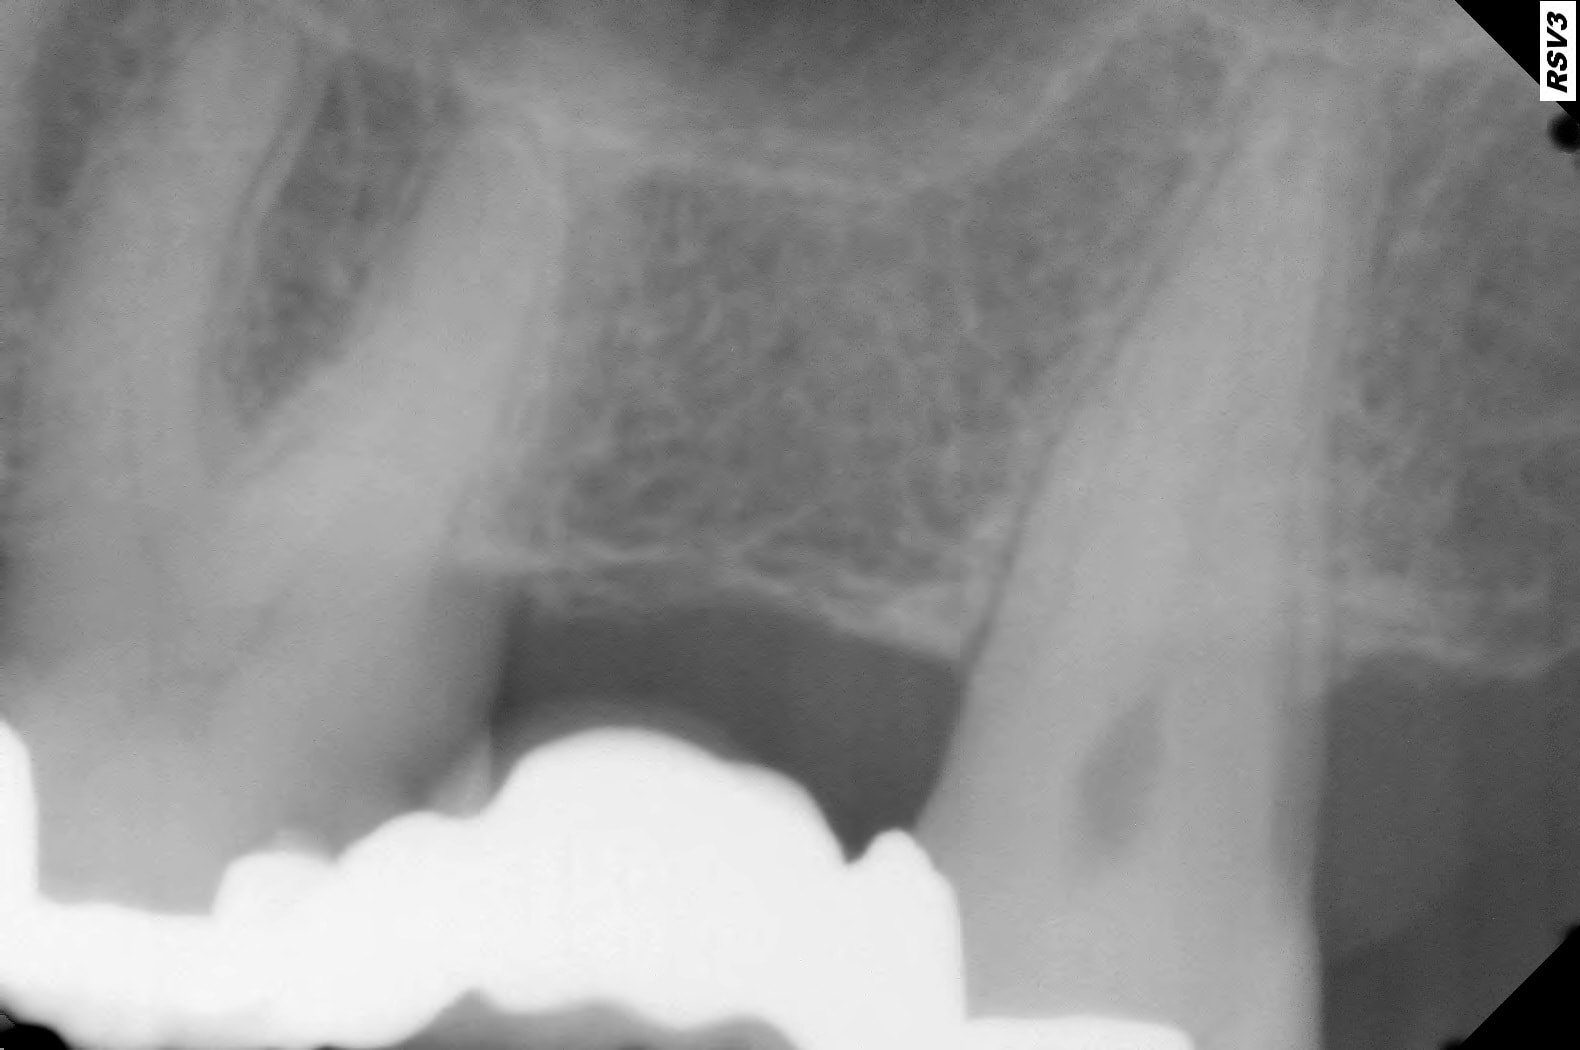

Je suis en train de réaliser un bridge 26 27 28 chez une patiente.

C'est suite à une reprise de carie sous l'ailette d'un vieux bridge collé .

Après la taille de 26 , j'ai choisi d'essayer de la garder vivante.

Malheureusement , une semaine après elle avait des douleurs importantes sur cette dent à la percussion et à la pression.

Je l'ai donc dévitalisée le 19/12/2024.

Suite à ce TR, elle présente des douleurs à la pression sur la dent 26 sans interruption, qui perdurent malgré un traitement antibiotique de 1 semaine début janvier.

J'ai fait un conebeam de la 26.

L'obturation des racines est correcte, il y a juste une petite image apicale au niveau de la racine palatine avec un léger dépassement de pâte.